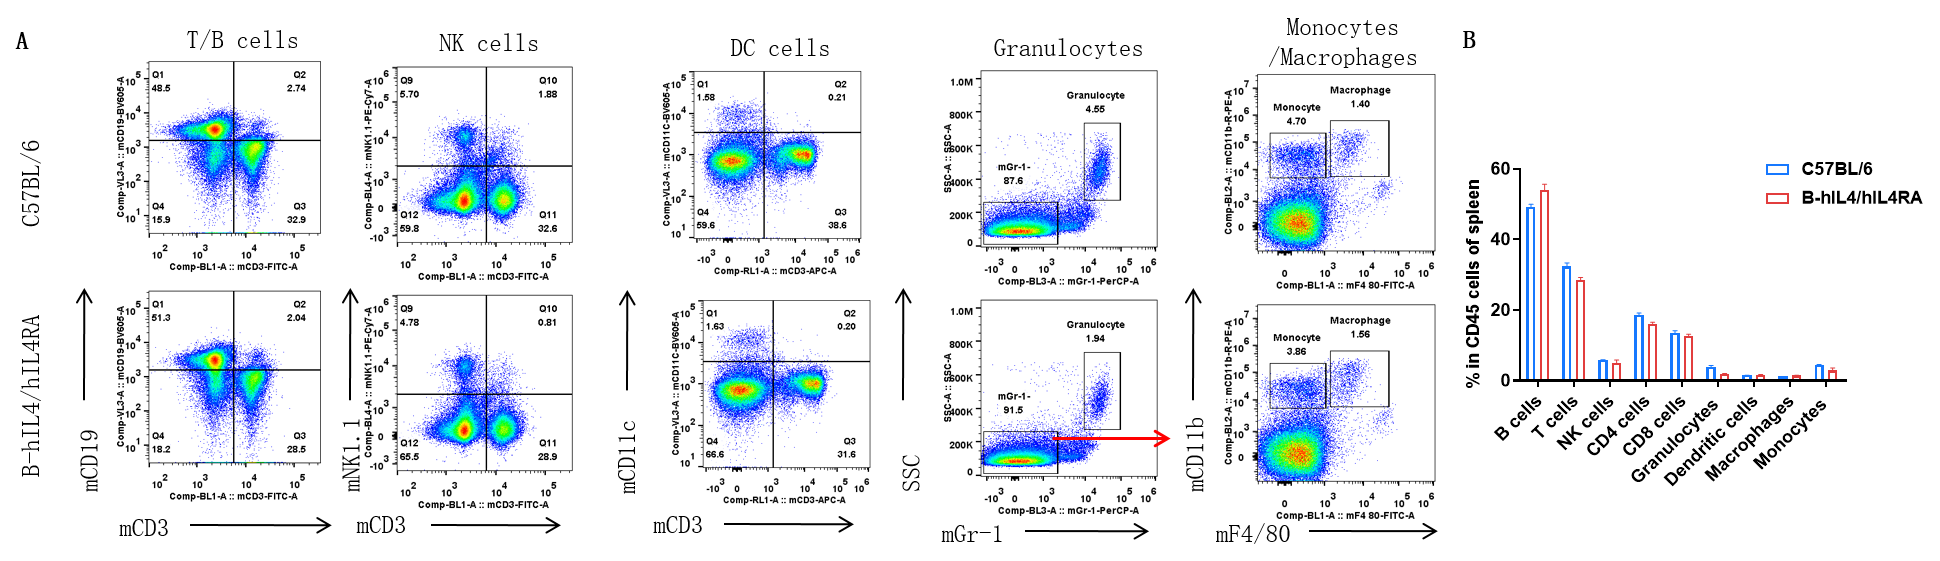

Analysis of spleen leukocyte subpopulations by FACS. Splenocytes were isolated from female C57BL/6 and B-hIL4/hIL4RA mice (n=3, 10-week-old). Flow cytometry analysis of the splenocytes was performed to assess leukocyte subpopulations. A. Representative FACS plots. Single live cells were gated for CD45 population and used for further analysis as indicated here. B. Results of FACS analysis. Percent of T, B, NK, Monocyte, DC and macrophage cells in homozygous B-hIL4/hIL4RA mice were similar to those in the C57BL/6 mice, demonstrating that introduction of hIL4 and hIL4RA in place of its mouse counterpart does not change the overall development, differentiation or distribution of these cell types in spleen.